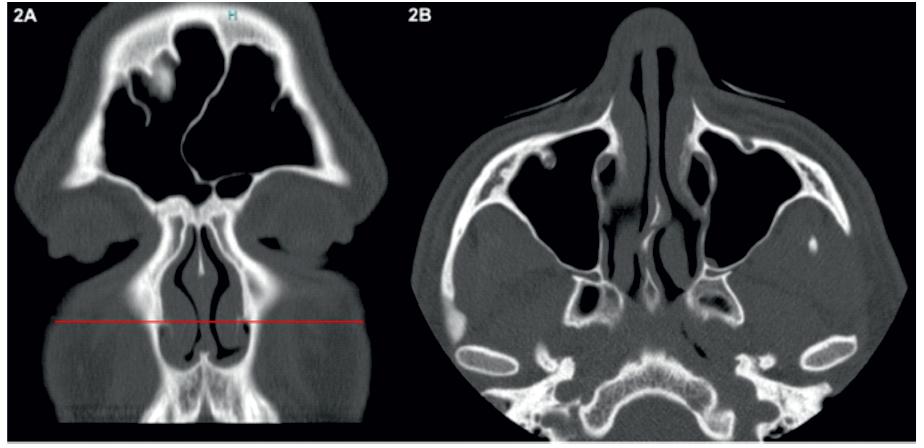

Os parâmetros morfométricos do RPL estudados neste trabalho foram todos analisados no plano axial correspondente à inserção do corneto inferior na apófise frontal da maxila (Figura 2).

Figura 2 Exemplo de como foi selecionado o plano axial utilizado para estudar os parâmetros morfométricos do recesso pré-lacrimal.